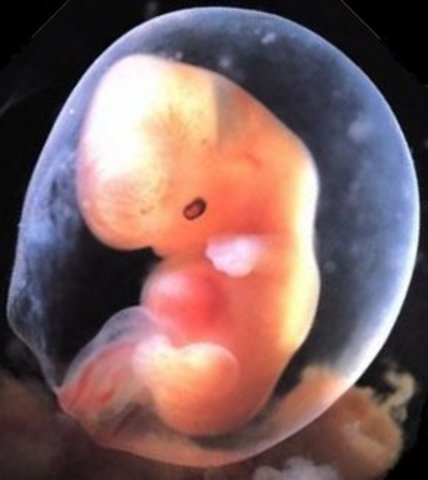

Week 5: Embryonic Stage Begins

Amniotic fluid building up, embryo grows from 2mm, by end of week embryo has doubled in size to about 4-5mm, egg has now completely grown into the mucous membrane of the uterus, a fibrin clot closes hole to uterus cavity, placenta is developing, embryo starts receiving oxygen and nutrition through the placenta. Cells making up the ovum are beginning to differentiate and specialize in areas of development. Ovum has now implanted into the uterine wall

• Week 6: Heart Begins to Beat

Week 6: Heart Begins to Beat

Embryo has reached a size of about 8mm, spinal cord is beginning to close, first blood cells and blood vessels are developing, pipe-shaped heart is formed and begins to beat, brain begins to divide into 5 parts, optic pits form the start of the developing eye, cells destined to be arms and legs are in place. Although not completely developed, all the major body organs and systems are formed

• Week 7: Arms and Legs Begin to Grow

Week 7: Arms and Legs Begin to Grow

Embryo is around 13mm, heart is beating with one chamber, dividing wall is formed in the heart, arm and leg buds begin to grow, lower jaw and vocal cords begin to form, mouth opening is formed, inner ear is being created, digestive tract is developing, navel string being created, lungs, liver, pancreas, and thyroid gland are being formed

• Week 8: Starts to Practice Moving

Week 8: Starts to Practice Moving

Embryo measures about 18mm in length, arm and legs are growing and location of elbows and toes are visible, feet and hand buds have appeared, starts to practice moving (not felt by mom until week 20), stomach is being made, face is beginning to take shape, baby's mouth and nostrils are starting to develop, teeth begin to develop, eyes can be seen as small hallows